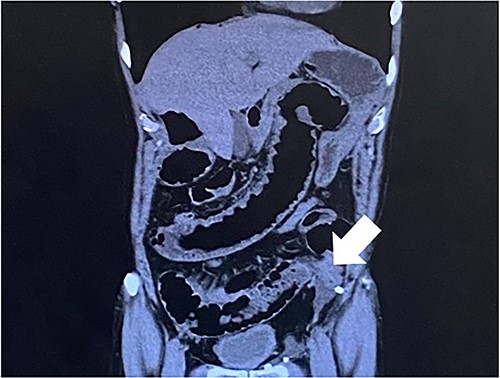

Computed tomography revealed caliber changes in the small bowel at the site of post-hernia repair in the left inguinal region (Figs 1 and 2), and the patient underwent laparoscopic surgery under general anesthesia. Intraperitoneal observation revealed that the peritoneal suture in the left inguinal region was detached, and a hole in the peritoneum had formed a hernial orifice (Fig. 4), causing SBO because of preperitoneal herniation (Fig. 3). The hernia was released, the peritoneal hole was sutured again and the surgery was completed. The postoperative course was good, and the patient was discharged from the hospital on the third postoperative day after reoperation.

The white arrow shows the site of caliber change in the small bowel (axial section image).